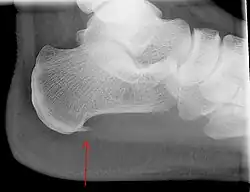

Подошвенная фасция (апоневроз) прикрепляется к пяточному бугру и головкам плюсневых костей, поддерживая продольный свод стопы. В вертикальном положении человека приблизительно половина массы его тела оказывает давление на эту фасцию, при этом наибольшее напряжение испытывают ткани в месте прикрепления к пяточному бугру. В связи с постоянной нагрузкой возможны микронадрывы фасции, которые в норме регрессируют самостоятельно. Однако в некоторых случаях постоянная микротравматизация может послужить причиной хронического асептического воспаления с болевым синдромом. На фоне плантарного фасциита, в качестве компенсаторной реакции, возможно образование краевых костных разрастаний (остеофитов), получивших название «пяточных шпор».

Ведущий симптом плантарного фасциита — боли в пяточной области, возникающие или усиливающиеся при нагрузке. Болевые ощущения более выражены в утренние часы. В большинстве случаев для диагностики плантарного фасциита достаточно анализа жалоб пациента, физикального осмотра и рентгенографии, позволяющих выявить наличие пяточной шпоры. Отсутствие пяточной шпоры в совокупности с пяточной болью требуют дифференциального диагноза, в первую очередь, с системными воспалительными заболеваниями (ревматоидный артрит, синдром Рейтера и др.), которые также могут дебютировать пяточной болью. Фасциит может осложняться переломами остеофитов.